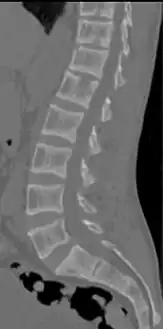

CT scan of the same case.[17]